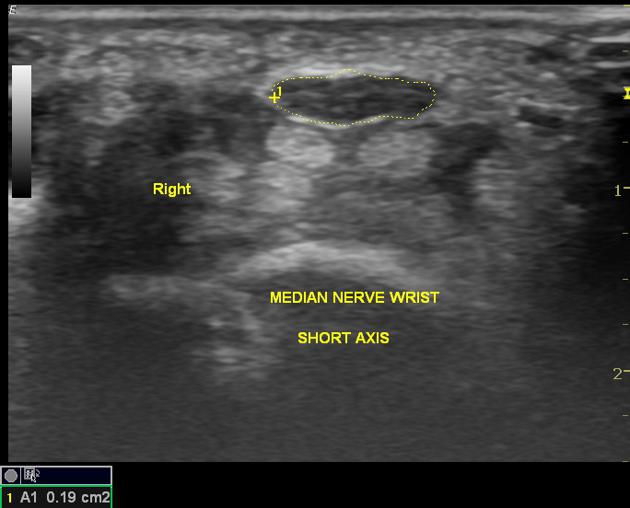

수근관 증후군은

염증으로 퉁퉁 부은

정중신경의 단면적(CSA)이

9-16㎟ 이상일 때

진단할 수 있습니다.

Ref> Sonography in the diagnosis of CTS: a critical review of the literature.Beekman R, Visser LH. Muscle Nerve. 2003 Jan; 27(1):26-33.

같은 손목터널 증후군이라도

단면적(Cross Sectional Area)이

10㎟ 인 환자도 있고

25㎟ 인 환자도 있고

다양합니다.